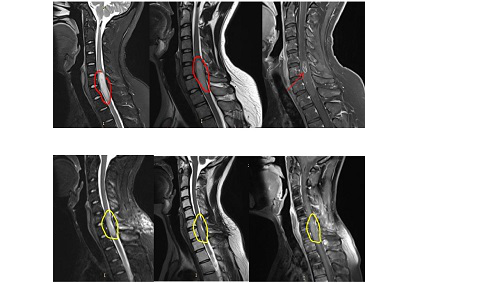

術(shù)前:頸痛、手臂麻木持續(xù)了半年,國(guó)內(nèi)專家一致認(rèn)為”手術(shù)困難太大,殘疾的可能性很大“。

術(shù)后:脊髓內(nèi)星形細(xì)胞瘤的瘤體強(qiáng)化部分被完整切除,腫脹效應(yīng)減輕。手術(shù)后的一天,醫(yī)院給予頸部外固定護(hù)理,動(dòng)不了但意識(shí)是清醒的,術(shù)后4天,已經(jīng)可以下地行走。術(shù)后10天,患者就出院回國(guó)進(jìn)行康復(fù)護(hù)理和后續(xù)治療了?,F(xiàn)在,患者的頸痛癥狀大有減輕,手臂麻木感也有所緩解,后續(xù)的復(fù)查也沒有發(fā)現(xiàn)腫瘤增長(zhǎng)和復(fù)發(fā)的情況。

髓內(nèi)腫瘤:術(shù)前T1加權(quán)釓增強(qiáng)矢狀位(a)和軸位(b)MRI掃描髓內(nèi)室管膜瘤。術(shù)中導(dǎo)航(c、d)的發(fā)現(xiàn)與MRI相似,顯示脊髓擴(kuò)大,無明顯水腫。中央室管膜也用術(shù)中導(dǎo)航很好地暴露了。